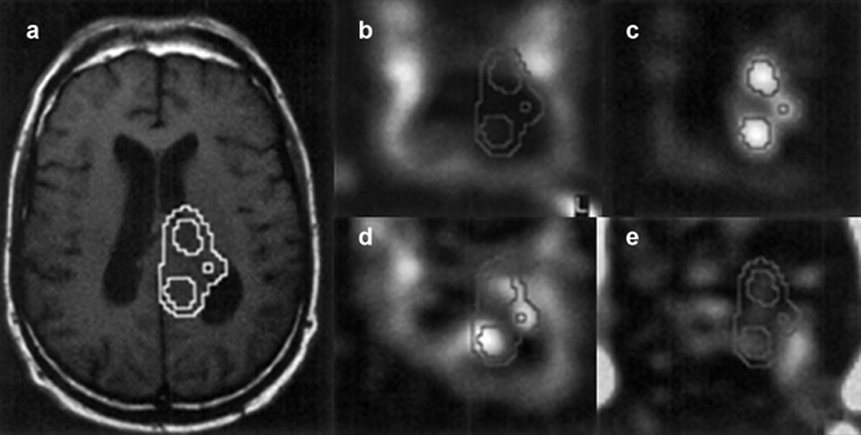

Figure 05-08:

Proton magnetic resonance spectroscopic imaging (MRSI) of a patient suffering from a high-grade glioma.

(a) Conventional T1-weighted spin echo MR image with overlayed choline contour.

Metabolite maps of (b) N-acetylaspartate, (c) choline, (d) creatine, and (e) lactate.

N-acetylaspartate is decreased in the tumor and the ventricles, whereas the choline level is elevated in the tumor. Regions with increased choline levels do not overlap regions showing lactate, which is an in­di­ca­tion of the lo­ca­tion of the active parts of the tumor.